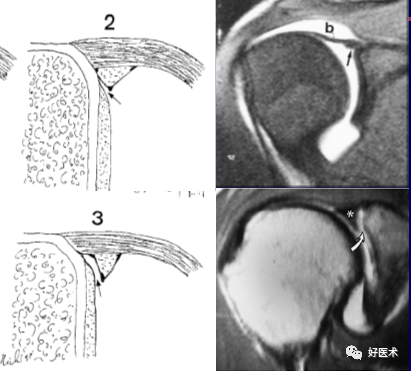

BLC 有三种类型:

-

Ⅰ型:BLC 牢固的与关节盂上极相连。

Ⅱ型:BLC 附着点在关节盂缘矢状面的内侧几毫米处。

Ⅲ型:盂唇在形态上与半月板相似。

盂下隐窝:Ⅱ型或Ⅲ型BLC所致盂唇与关节盂之间的隐窝,位于12点钟方位。

盂下孔:需与盂下隐窝鉴别,位于2点钟方向